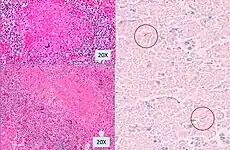

Histopathology, showing epithelioid granulomas with multinucleated giant cells and acid-fast bacilli -